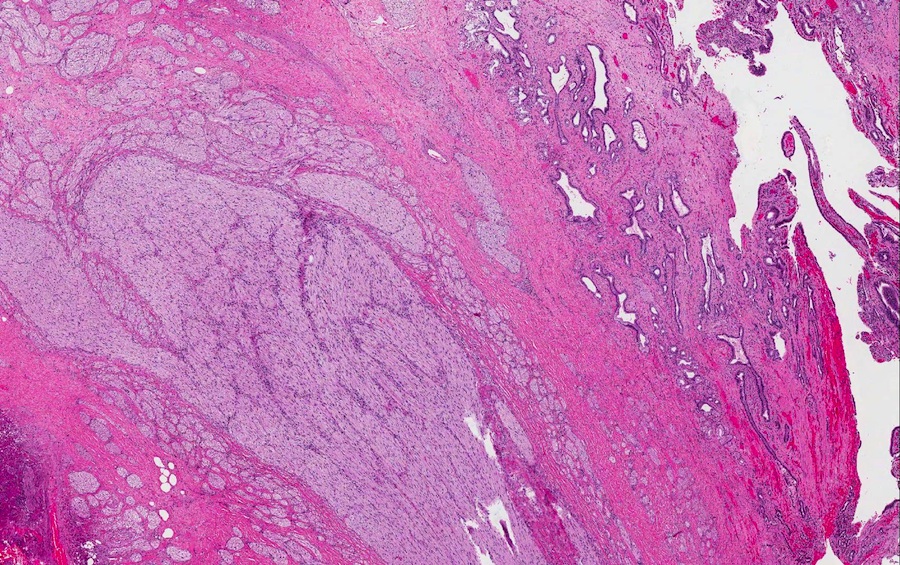

Microscopic images:

Both cases showed disorganized and thickened nerve bundles composed of spindle shaped cells, without atypia. Case A also showed a focal foreign body type giant cell reaction adjacent to the disorganized nerve bundles and a strongly immunoreactive S100 stain.

Histology typically shows hyperplastic nerve bundles, positive for S100.

Microscopic images:

Both cases showed disorganized and thickened nerve bundles composed of spindle shaped cells, without atypia. Case A also showed a focal foreign body type giant cell reaction adjacent to the disorganized nerve bundles and a strongly immunoreactive S100 stain.

Histology typically shows hyperplastic nerve bundles, positive for S100.